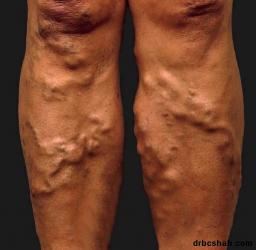

Varicose veins, also known as varicoses or varicosities, occur when your veins become enlarged, dilated, and overfilled with blood. Varicose veins are often painful and have a bluish-purple or red color. Often, varicose veins appear swollen and raised.